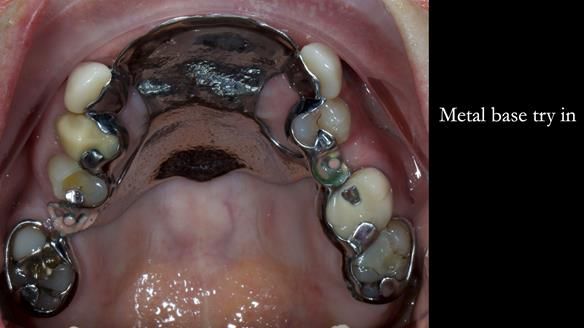

This is one of those cases that reminds me why I love removable prosthodontics. Pam was an absolute joy to treat — we were on the same page throughout. Her old upper flexible denture was loose, uncomfortable, and unaesthetic. We replaced it with a carefully designed metal-based upper partial denture/splint and new porcelain-bonded-to-zirconia (PBZ) crowns for the canines. The result is stable, comfortable, and natural-looking.

- Diagnosis and plan – Flexible upper denture ill-fitting with poor stability, retention, and appearance. Plan: metal-based upper partial denture/splint with lighter porcelain-bonded-to-zirconia crowns on UR3 and UL3.

- Metalwork framework try-in – to verify fit, path of insertion, and support.